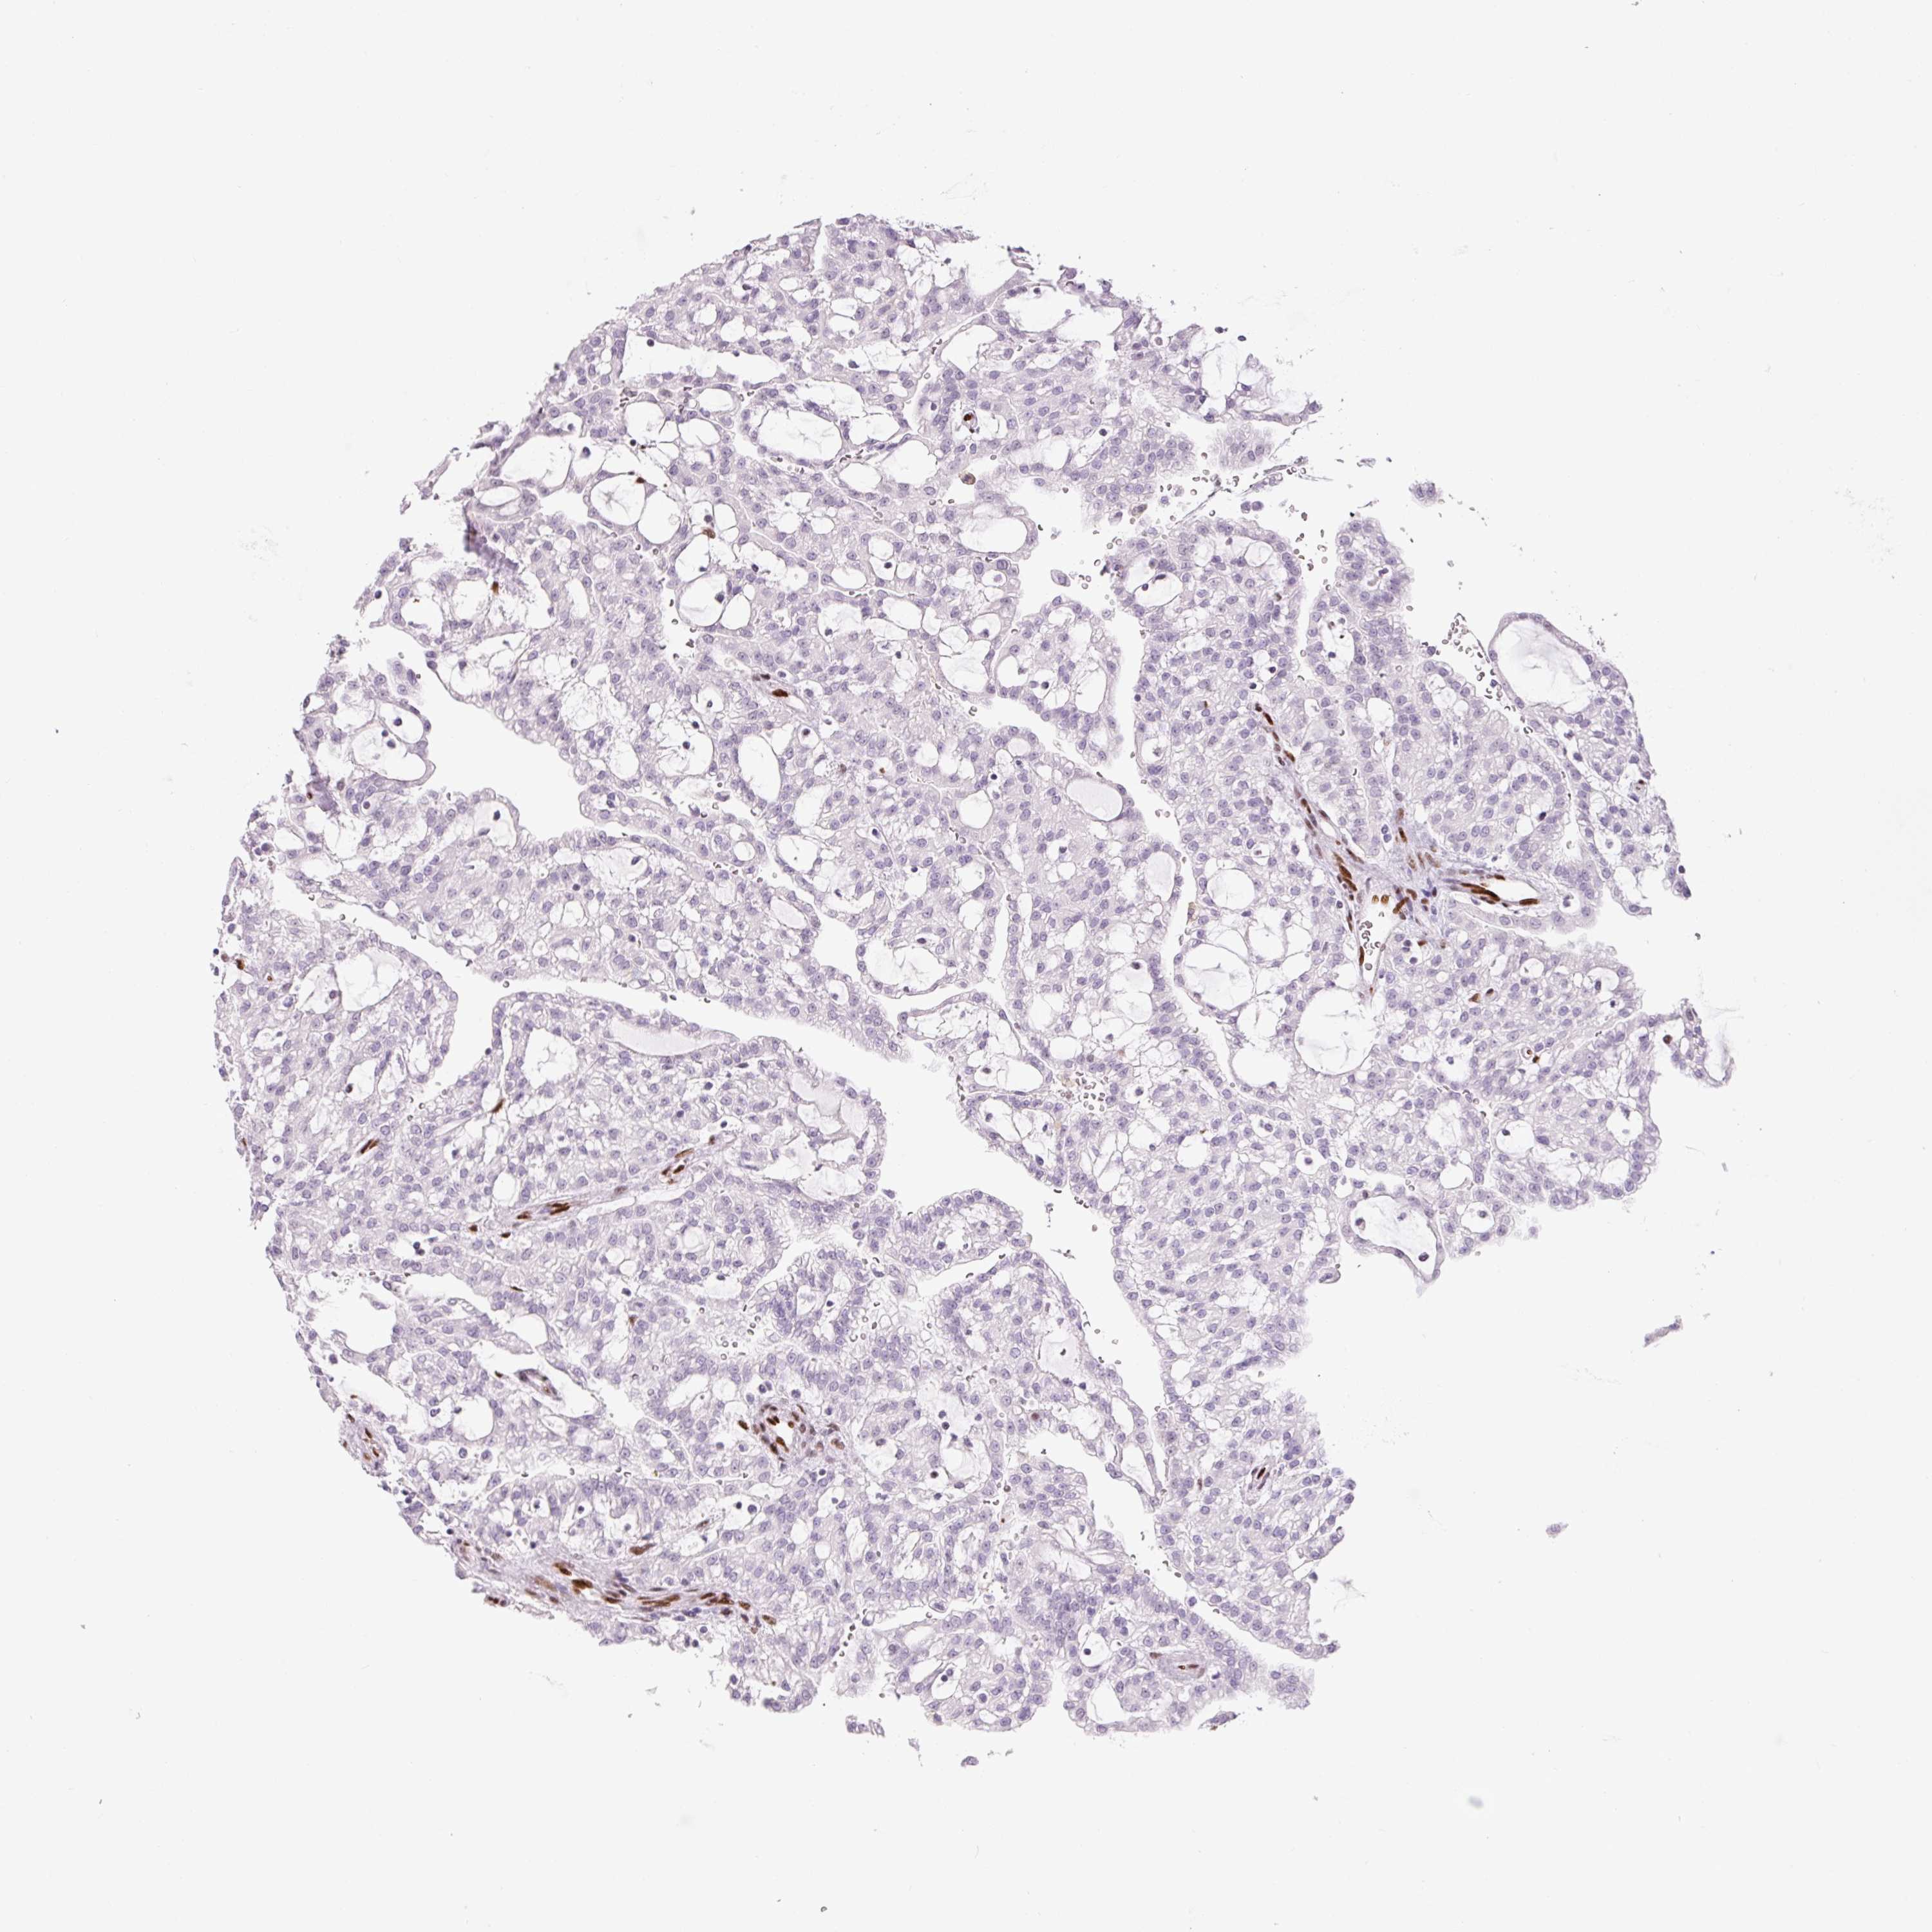

KIDNEY RENAL PAPILLARY CELL CARCINOMA (TCGA) - Interactive survival scatter ploti

The Survival Scatter plot shows the clinical status (i.e. dead or alive) for all individuals in the patient cohort, based on the same data that underlies the corresponding Kaplan-Meier plots. Patients that are alive at last time for follow-up are shown in blue and patients who have died during the study are shown in red.

The x-axis shows the expression levels (FPKM) of the investigated gene in the tumor tissue at the time of diagnosis. The y-axis shows the follow-up time after diagnosis (years). Both axes are complimented with kernel density curves demonstrating the data density over the axes. The top density plot shows the expression levels (FPKM) distribution among dead (red) and alive patients (blue). The right density plot shows the data density of the survived years of dead patients with high and low expression levels respectively, stratified using the cutoff indicated by the vertical dashed line through the Survival Scatter plot. This cutoff is automatically defined based on the FPKM cutoff that minimizes the p-score. The cutoff can be changed by dragging the vertical line or by entering a cutoff value in the square labeled "Current cut-off".

Under the Survival Scatter plot the p-score landscape (black curve; left axis) is shown together with dead median separation (red curve; right axis). Dead median separation is the difference in median mRNA expression between patients who have died with high and low expression, respectively. It is calculated as follows: median FPKM expression of dead patients with high expression - median FPKM expression of dead patients with low expression. This is intended to aid the user in visually exploring custom cutoffs and the associated p-scores and dead median separation.

Individual patient data is displayed and can be filtered by clicking on one or more of the category buttons on the top of the page. Categories describing expression level and patient information include: high, low, alive, dead, female, male and tumor stages. The scale of the x-axis can be toggled between linear and log-scale by clicking on the "x log" button. Mouse-over function shows TCGA ID, patient information and mRNA expression (FPKM) for each patient.

& Survival analysisi

Kaplan-Meier plots summarize results from analysis of correlation between mRNA expression level and patient survival. Patients were divided based on level of expression into one of the two groups "low" (under cut off) or "high" (over cut off). X-axis shows time for survival (years) and y-axis shows the probability of survival, where 1.0 corresponds to 100 percent.

ZEB1 is not prognostic in Kidney Renal Papillary Cell Carcinoma (TCGA)